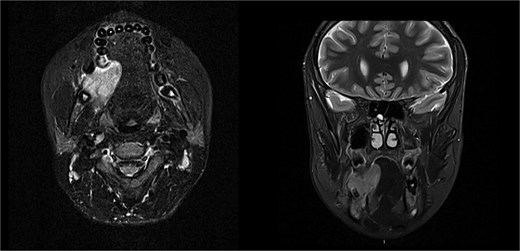

Solid enhancing right osteolytic mandibular lesion with small necrotic components within it. Infection/abscess less likely due to absence of fat stranding/rim enhancement (MRI).

MRI is the optimal modality for diagnosing intraosseous myofibroma of the mandible [9, 10]. MRI provides superior soft tissue contrast and anatomical information, which is crucial for assessing the extent of the lesion and its relationship with adjacent structures. MRI findings include low signal intensity on T1-weighted images and variable signal intensity on T2-weighted images, with peripheral enhancement after gadolinium administration [10]. MRI avoids radiation exposure, which is paramount considering that this tumour commonly affects a younger patient cohort. CT is valuable for evaluating bone involvement and detecting cortical destruction, calcifications, and the extent of bone erosion. OPGs are useful as an initial imaging modality to identify the presence of a mandibular lesion and its effect on teeth.